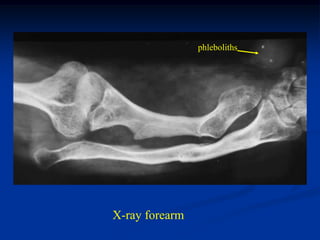

Case #584

33 year male

Maffucci’s disease

X-ray tibias

phleboliths

X-ray forearm